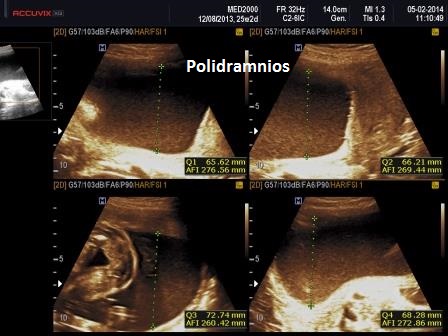

6) polidramnios.